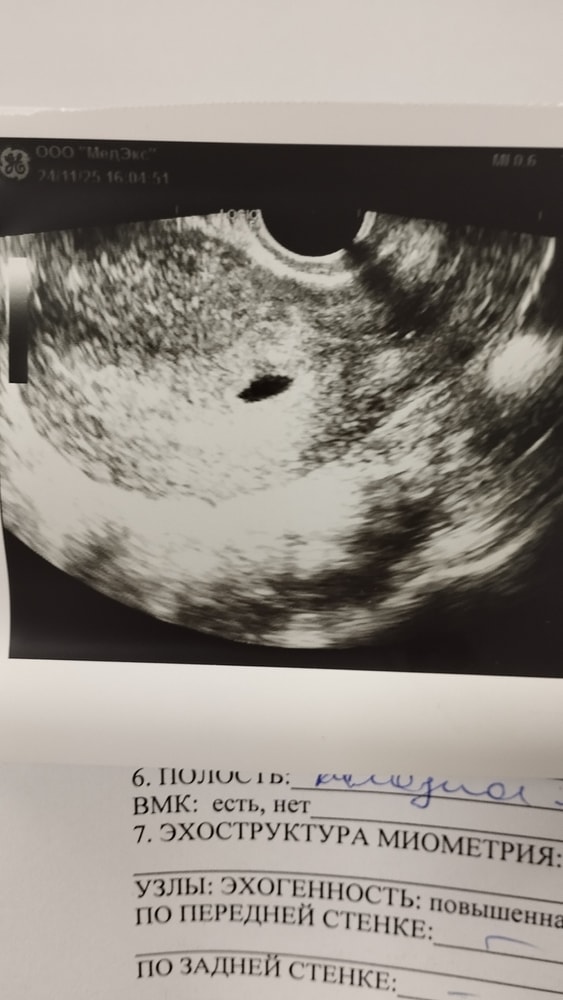

Доброе утро! Вчера была на УЗИ, подтвердить маточную беременность, так как в анамнезе внематочная, поэтому пошла я раненько) В общем нашли пя, но размеры какие-то странные, у девушек поменьше на этом сроке вроде бы находили. ПЯ 13мм, желточный м. 2 мм. Может погрешность? Срок сказал врач даже не поставлю, насчитал примерно 3 недельки😄 главное, что там, где надо🙏

У меня в 4,4-4мм, а в 5.6-14 мм. Вы узисту доверяете?

в 7.0 малыш на 6.4 пя на 8.4 было

в 7.0 малыш на 7.2, пя на 9.2 было

У меня с третьей в 5+3 пя было 5 мм и не было жм. Может там для двоих домик растет)))))

У меня в 4 Нед 4 дня нашли два одно 5,1 другое 4,3, скоро пойду еще узнаю остались ли оба или один остался. А раз у вас такое больше может у вас многоплодная беременность?

У меня в 5 н было пя 5,8 мм)